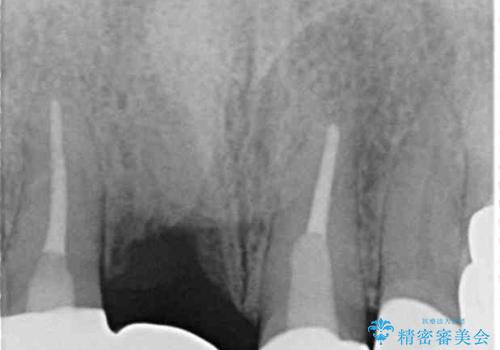

検査の結果、右前歯の歯根が縦に破折していることが分かりました。

破折している歯は抜歯をし、歯肉が窪んでしまうので、傷口の治りを待って、歯肉移植を行うこととしました。